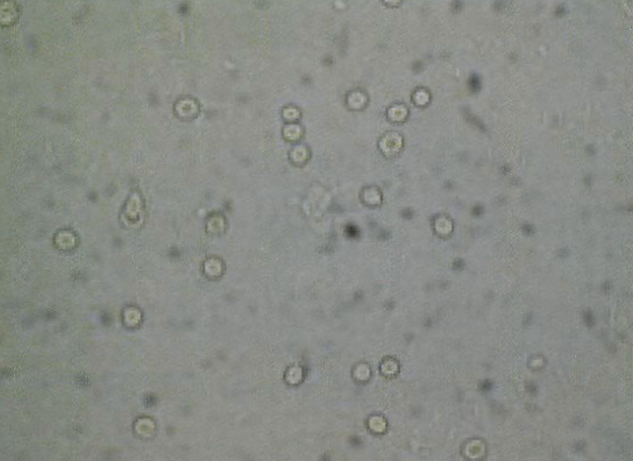

結石破砕治療の実際 – Radiology@Home。尿路結石の治療について | 医療法人社団實理会 東京国際大堀病院。尿路結石外来|尼崎市 おかだ腎泌尿器・ペインクリニック| 阪神。ぷっち おまとめ2袋 白米10キロ。尿路結石症(腎結石・尿管結石)の治療法 - 船橋クリニック 千葉。体外衝撃波結石破砕装置(ESWL)|焼津市立総合病院。尿路結石の検査 - 船橋クリニック 千葉県泌尿器科 尿路結石症。痛みを乗り越えた者だけが手にする秘宝商品説明これは単なる石ではありません。長きにわたり忍耐と痛みを経験した末、身体から生まれた奇跡の結晶です。賢者の石と呼ばれるにふさわしい、神秘的な輝きを放つ逸品!その力強い存在感は、あなたのコレクションに一層の深みを与えることでしょう。おすすめポイント•世界に一つだけのオリジナル品!•痛みを耐え抜いた歴史を感じられるストーリー付き•お守りやアクセサリーの材料にも最適こんな方におすすめ!•面白グッズ好きな方•他人とは違うコレクションを目指す方•人生の痛みを乗り越える象徴が欲しい方これを手にすることで、あなたも「賢者」の仲間入りを果たせるかも?一点限りの出品ですので、お見逃しなく!。尿管結石の最新治療技術 - Genspark。尿路結石症 – 社会医療法人 北腎会 坂泌尿器科千歳クリニック。尿管結石の最新治療技術 - Genspark。巨大腎結石への挑戦 | 研究報告 | 医療法人社団實理会 東京国際。尿路結石(尿管結石、腎臓結石、膀胱結石)の原因や治療について。尿路結石」について|市立貝塚病院